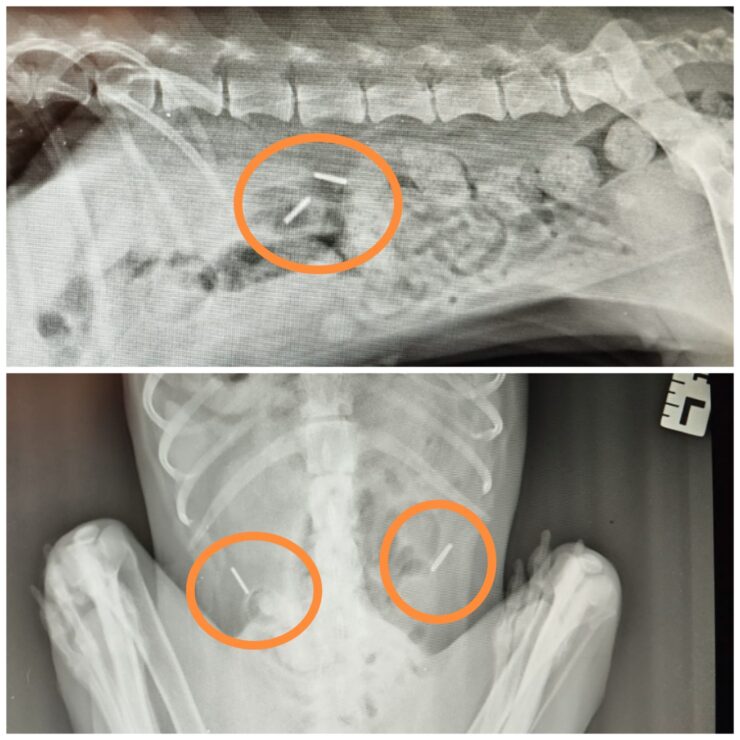

Pisaliśmy już o tym, że podczas ostatnich badań u Lilki wykryto dwa ciała obce w organizmie. Wszystko wskazuje na to, że są elementy metalowe – nie wyglądały jak śrut, ale trudno było jednoznacznie określić, czym są. Teraz, po badaniu USG, wiemy więcej – jeden z tych elementów mógł przedostać się do jelit..

Na tym etapie nie wiadomo, czy powoduje stan zapalny lub zagraża ich drożności. Tak naprawdę dopiero operacja pozwoli ocenić, czy to ciało obce jest bezpieczne do usunięcia, czy zdążyło już uszkodzić tkanki 🥺.

USG pokazało, że jedna z nerek Lilki jest mocno powiększona i napięta. To oznacza poważne ryzyko – może dojść do jej pęknięcia i w konsekwencji do groźnego dla życia zatrucia całego organizmu. Diagnoza brzmi: wodonercze. Ile jeszcze ta biedna, skrzywdzona przez los i ludzi sunia musi znieść? 💔